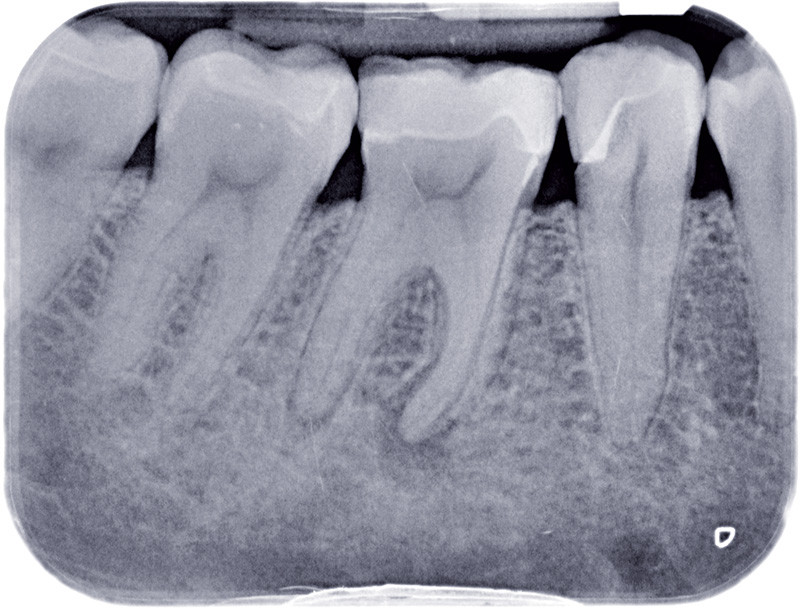

Le Dr Stéphane Simon dans cette nouvelle réponse d'expert revient sur la lésion apicale ou parondie apicale traitée tous les jours par les praticiens. Cette grosseur bénigne qui survient au niveau de la racine dentaire est provoquée par le système immunitaire On l'appelle kyste apical, granulome, lésion d'origine endodontique ou encore lésion apicale

Management of Apical Periodontitis Healing of Posttreatment Periapical Lesions Present 1 Year. Le granulome dentaire est une lésion inflammatoire à la racine d'une dent, causée par une infection bactérienne Aujourd'hui, plongeons-nous dans l'univers complexe d'une affliction dentaire relativement commune mais souvent mal comprise: la lésion apicale

Figure 1 from Endodontic Periapical Lesion An Overview on the Etiology, Diagnosis and Current. Le Dr Stéphane Simon dans cette nouvelle réponse d'expert revient sur la lésion apicale ou parondie apicale traitée tous les jours par les praticiens. Le traitement peut inclure une intervention endodontique ou une extraction.